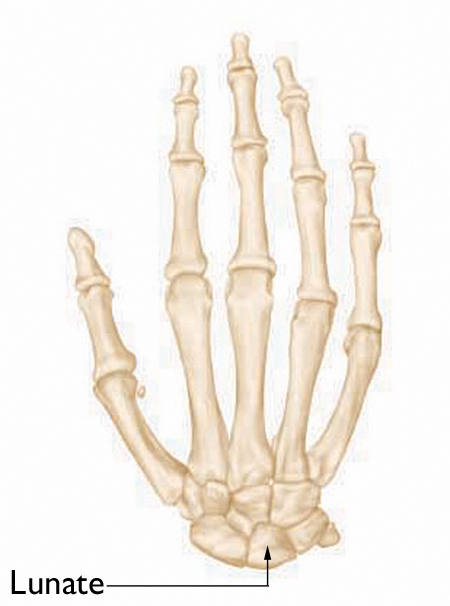

Normal anatomy of the hand and wrist

Normal skeletal anatomy of the hand and wrist. The lunate is one of the small bones in the wrist.

Kienböck's disease is a condition where the blood supply to one of the small bones in the wrist, the lunate, is interrupted. The lunate is a carpal bone.